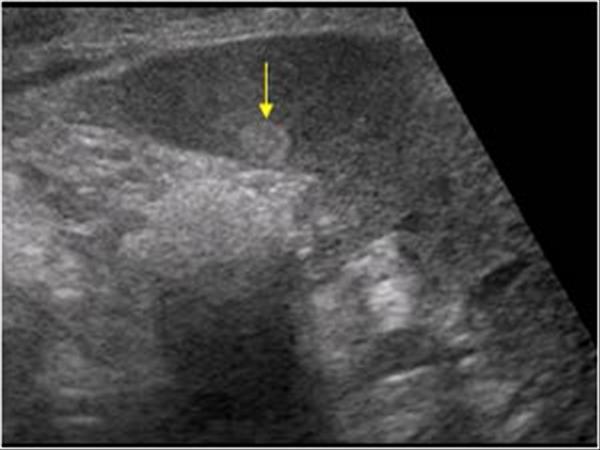

Accessory Spleen

Splenic granulomas

focal lesions resulting from previous infection

Hemangioma

Splenic infarct

common in patients with bacterial endocarditis and splenic artery aneurysms

general abdominal sepsis

Splenic Abscess

Splenic Artery Aneurysm